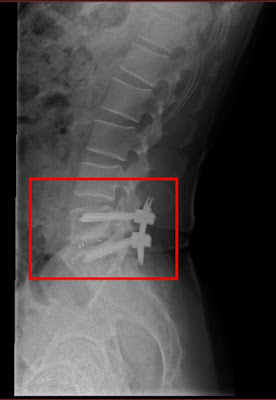

老先生家屬說他原本身體健壯,活動自如,但前兩年腰臀痛後檢查是腰椎滑脫,結果這兩年開了四次刀(包第一次括離譜的開錯部位的刀),結果,經歷四次開刀後,老先生又仍是腰腿痛麻,原本的疼痛沒有消失不說,幾次開刀後,腰上長達幾十公分刀疤,及腰椎上釘了18支鋼釘,讓老人家每天都痛不欲生,老先生家屬束手無策,卻又不知如何解決問題。

第三慘,第四次開刀完成,打了18支鋼釘,背後刀疤數十公分,鎮日疼痛,